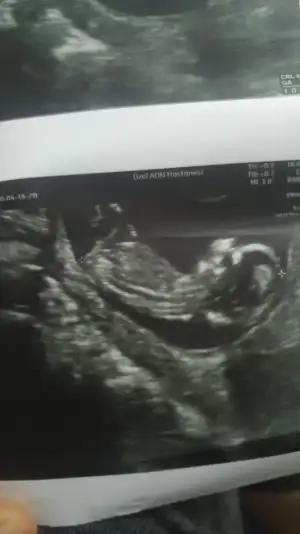

akadaşlar merhaba, ultrason görüntülerini paylaşsam bakabilir misiz.? meraktan çatlıyor insan 😍

Ultrason görüntülerimiz😍

• C5D6BCE4-511E-4694-BA9C-FAD0D1AB8020.webp

C5D6BCE4-511E-4694-BA9C-FAD0D1AB8020.webp

31,7 KB · Görüntüleme: 56

• A5C22EF2-16FD-44B6-BFCC-DA2322ACF2F8.webp

A5C22EF2-16FD-44B6-BFCC-DA2322ACF2F8.webp

17,5 KB · Görüntüleme: 50

• C4139B20-F0FF-4AB4-AFDF-3A75D4DD56C7.webp

C4139B20-F0FF-4AB4-AFDF-3A75D4DD56C7.webp

27,9 KB · Görüntüleme: 57

yaa 😍 bende kız diye gördüm ama emin olamadım. bu nub teorisi inşallah doğrudur 😂 allah gönlümüze göre versin 😊 senin bebişin cinsiyeti kesinleşti mi peki

Yok canım 14 de gittim giremedi kemik.yapısı kız dedi ama kordon un arkasında bir şey de var sanki dedi ogrenemdim inşaallah bu teori doğrudur da kız olur 😂😂